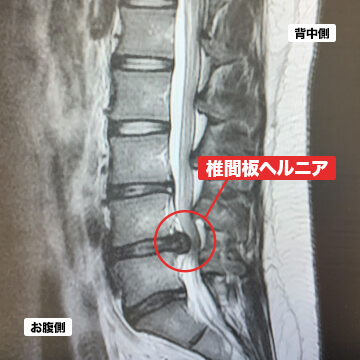

- 腰椎椎間板ヘルニア

腰椎椎間板ヘルニアとは、腰と腰の間にある椎間板と呼ばれる組織に傷が入り、中の髄核が神経に飛びだすことを言います。ヘルニアは自然に治癒する場合もありますが、再発を繰り返すと慢性的に腰痛や坐骨神経痛等の症状が現れることが多いです。